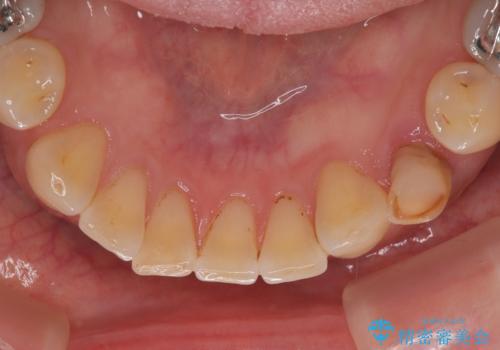

診査の結果、左下に残存していた乳犬歯が水平的に破折しており、残念ながら保存は困難な状態でした。

また、右下にはスペースがあり、左上にも乳犬歯が残存しているという状態で、治療方法としては矯正治療を含めた複数の選択肢が考えられました。